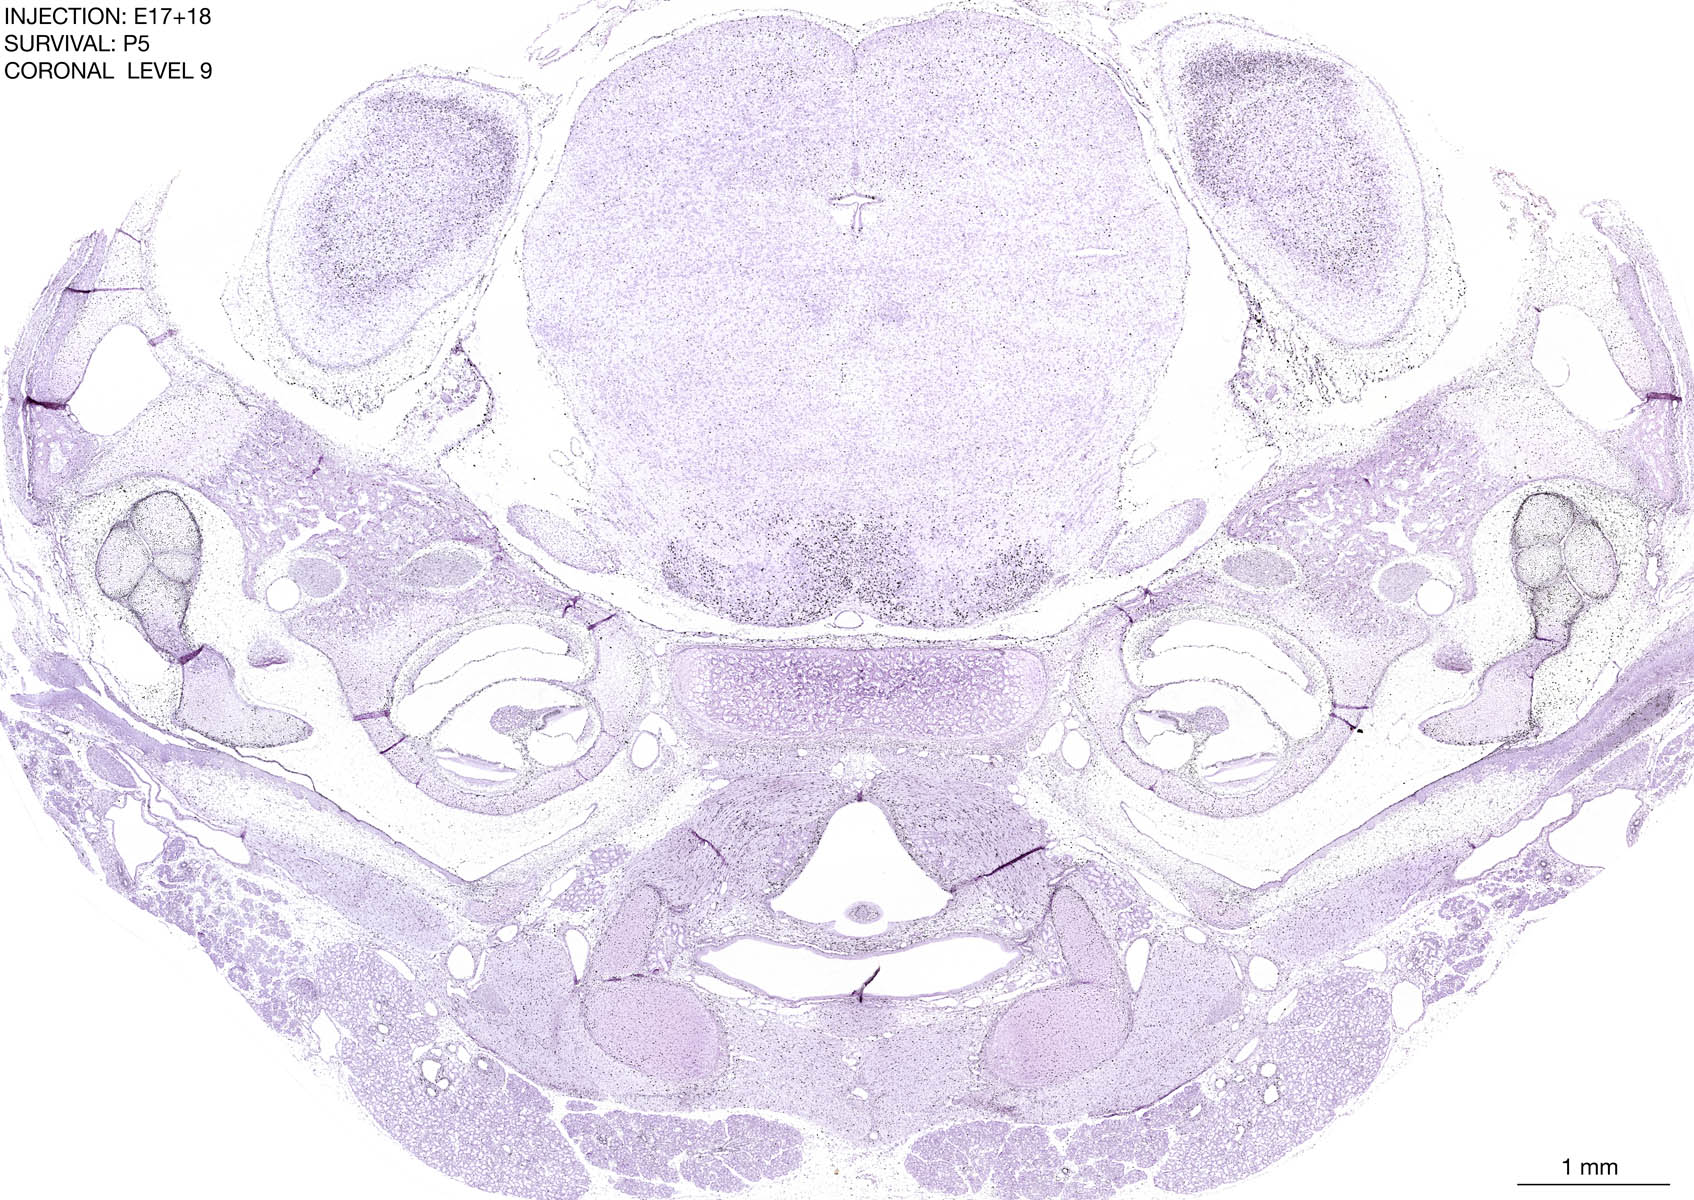

E17+18 P5 Survival The images below are from the brain of a rat that was exposed to tritiated thymidine on E17+18 and survived to P5. Download: Large | High Res Download: Large | High Res Download: Large | High Res Download: Large | High Res Download: Large | High Res Download: Large | High Res Download: Large | High Res Download: Large | High Res Download: Large | High Res Download: Large | High Res Download: Large | High Res Download: Large | High Res Download: Large | High Res Download: Large | High Res Download: Large | High Res Download: Large | High Res Download: Large | High Res Download: Large | High Res Download: Large | High Res Download: Large | High Res Download: Large | High Res Download: Large | High Res Download: Large | High Res Download: Large | High Res Download: Large | High Res Download: Large | High Res